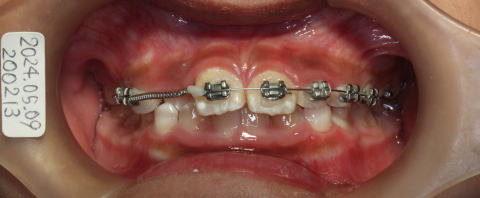

2024-05-09

12番が入る空間が出来たので咬合挙上して、21番を前に出すようにする。

12番の部分が狭いのでバネで大きくする。